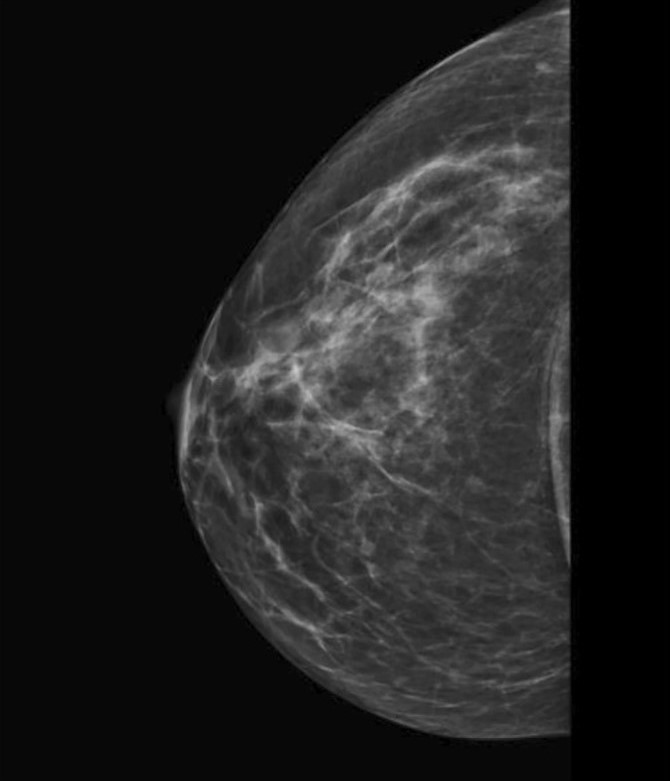

Сосудистые кальцинаты определяются на маммограммах как параллельные гиперденсные линии по ходу стенок сосудов. Их также называют кальцинатами Мёнкеберга, они поражают среднюю оболочку сосуда [13, 14] (Рис.2).